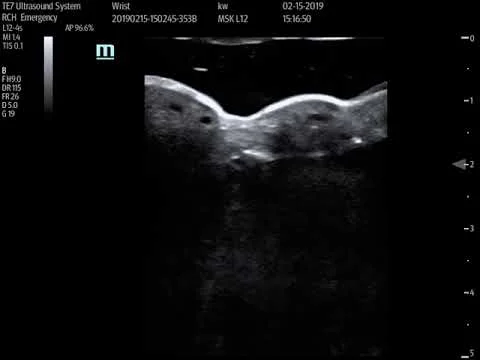

Distal radius fracture